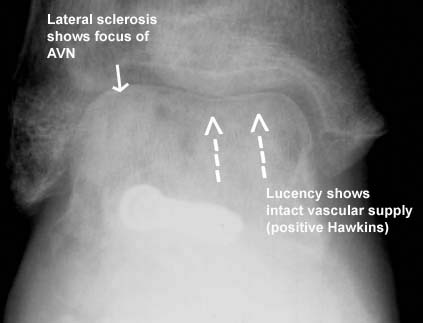

Talar neck fractures are high-energy injuries that have a high incidence of associated fractures and subsequent talus avascular necrosis. The typical mechanism of injury is a high-energy axial load delivered through a dorsiflexed foot. The talus is one of two hindfoot bones and is covered almost entirely with cartilage. The blood supply to the talus is tenuous, easily disrupted with injury, and comes from three sources: the posterior tibial artery via the artery of the tarsal canal (dominant supply), the anterior tibial artery, and the perforating peroneal artery via the artery of the tarsal sinus. Talar neck fractures are classified according to the Hawkins classification (Illustration A). Higher classification injuries are associated with a higher rate of avascular necrosis. Treatment for displaced fractures (Hawkins II-IV injuries) is open reduction and internal fixation. Unfortunately, owing to the high-energy nature of the injury and the tenuous blood supply to the talus, these injuries are fraught with complications. Almost all patients go on to develop subtalar arthritis, and AVN develops in 20 - 100% of patients with Hawkins III and IV fracture patterns. Intact vascularity can be assessed with a mortise radiograph 6-8 weeks after injury. The presence of a subchondral lucency indicates active resorption of subchondral bone and thus, intact vascularity (Illustration B).

Figure A demonstrates a Hawkins III talar neck fracture, with associated subtalar and tibiotalar dislocation.

Illustration A is an outline of the Hawkins classification. Illustration B is a labeled radiograph demonstrating the Hawkins sign, which is an indication of intact vascularity.